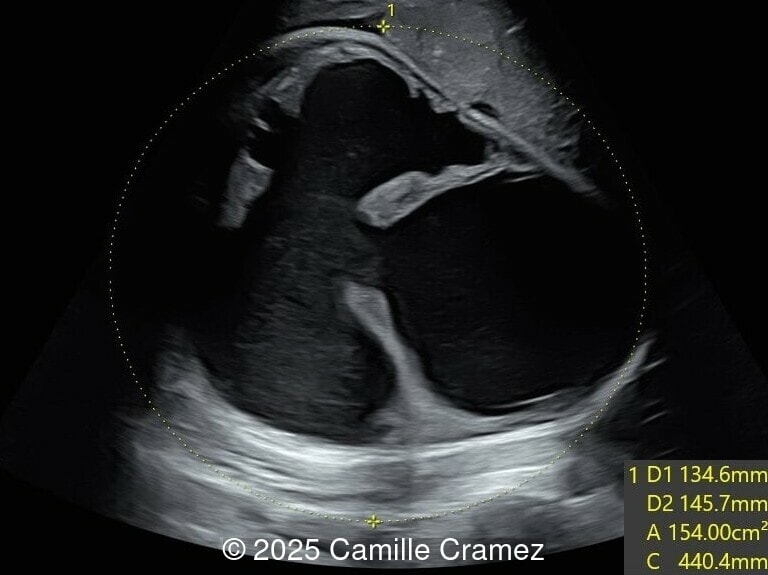

Axial image of the fetal abdomen

Image 12 Axial image of the fetal abdomen

Image 13 Axial image of the fetal abdomen

Our prenatal ultrasound revealed a male fetus with megabladder, dilation of both ureter and kidneys, and thinned kidney parenchyma consistent with Lower Urinary Tract Obstruction (LUTO).  Additional findings suspected on ultrasound and confirmed on computed tomography included:

The diagnosis of PBS is often made in the second trimester of pregnancy, although it has been described as early as 11 weeks of gestation [20]. The most frequent ultrasound findings are a large, thin-walled bladder accompanied by bilateral hydroureter/hydronephrosis, dysplastic kidneys with echogenic renal parenchyma and renal cortical cysts, and abdominal wall laxity which is better viewed after bladder decompression [21]. Cryptorchidism can be detected prenatally by 28 to 30 weeks gestation when the testes descend into scrotum. There may be a patent urachus, visible as a cystic connection between bladder and umbilicus. Oligohydramnios is a frequent finding, which makes it difficult to visualize the associated anomalies.